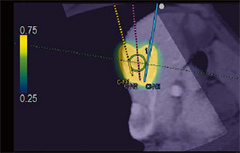

・E-field Simulator

RFA治療時の電極の配置から決定される電気的物理量(電場)をCTなどの画像上に表示します。複数本穿刺の際にもあらゆる電極配置に合わせて電場をシミュレーション可能なので,穿刺ライン検討の自由度が大幅に高まります。

これまでの手技を大幅に改善することが期待されます。